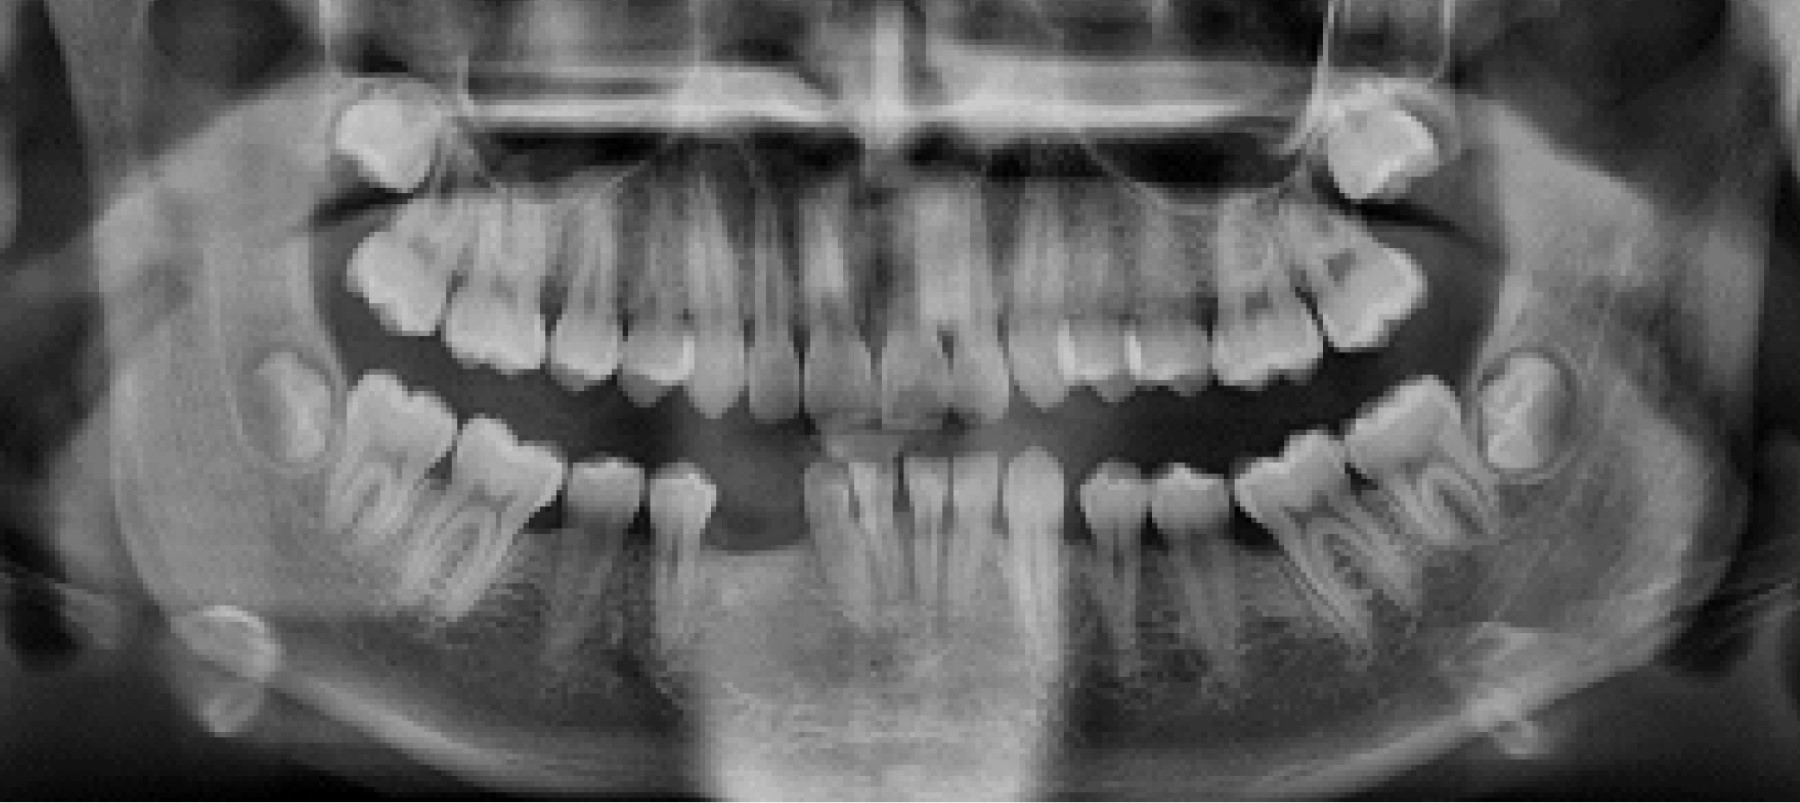

Paciente de 12 años de edad acude en el año 2015, junto a su madre, a la Clínica de Odontopediatría de la Universidad de Concepción para un examen de rutina. El paciente se atendía previamente en controles odontológicos en el área privada y poseía exámenes imagenológicos del año 2012 que evaluaban el desarrollo de la dentición (Figura 1).

Es útil analizar el grado de inclinación canina en una radiografía panorámica en el diagnóstico precoz de la transmigración. El ángulo de inclinación canino entre 30o y 50o puede indicar la presencia de la transmigración. Cuando es mayor de 50o indicaría una clara presencia de una futura transmigración.8 En la Figura 1 se observa una ligera mesioinclinación de los caninos inferiores, aunque no son concluyentes o inducen a sospechar de una futura transmigración en nuestro caso.

Figura 1